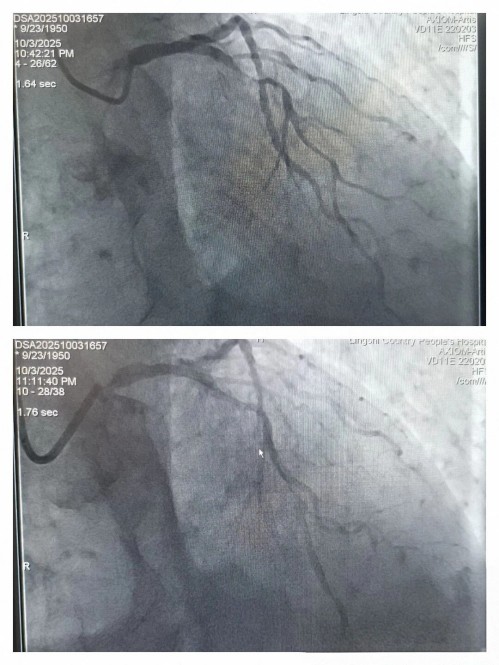

第三位急诊患者球囊扩张后

择期处理病变

第四位患者行球囊扩张